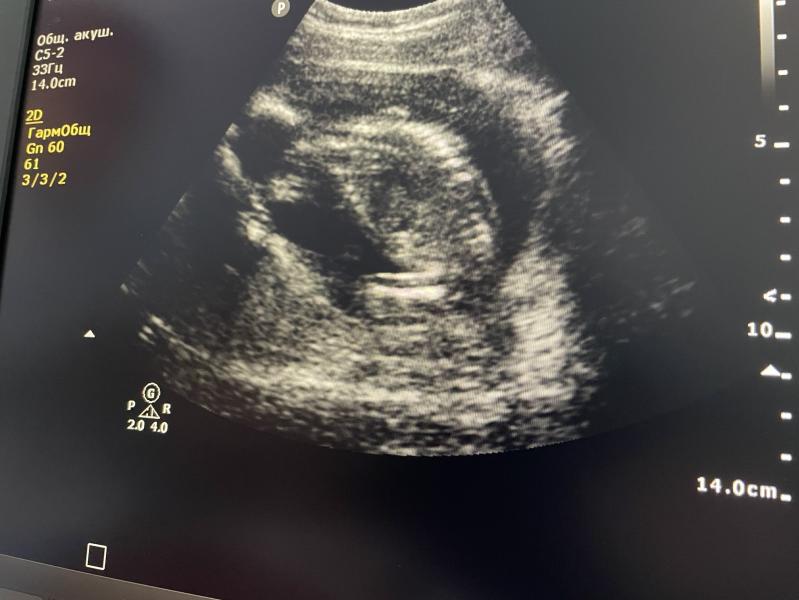

Сегодня на скрининге малыш на весь экран показал яйца))) в очередной раз)

Просто два яйца))))

А потом он повернулся к доктору попой и показал ей анус, прям дырку🤦🏻♀️

Это после того как она начала ворчать, что он не хочет ей лицо показывать и принялась сильнее водить датчиком.

Мистер Китенок, он же Пирожок

Ибо в 30,3 - 1755 гр.

Собственно на экране одни щеки.